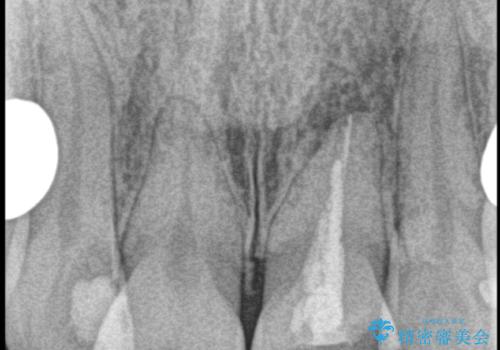

- 自転車で転倒してしまい、前歯を折ってしまい、痛みと見た目の改善を希望され来院されました。

もともと根管治療の為されて歯が折れてしまっているので、根管治療を行い審美的なセラミック治療を行う治療計画としました。